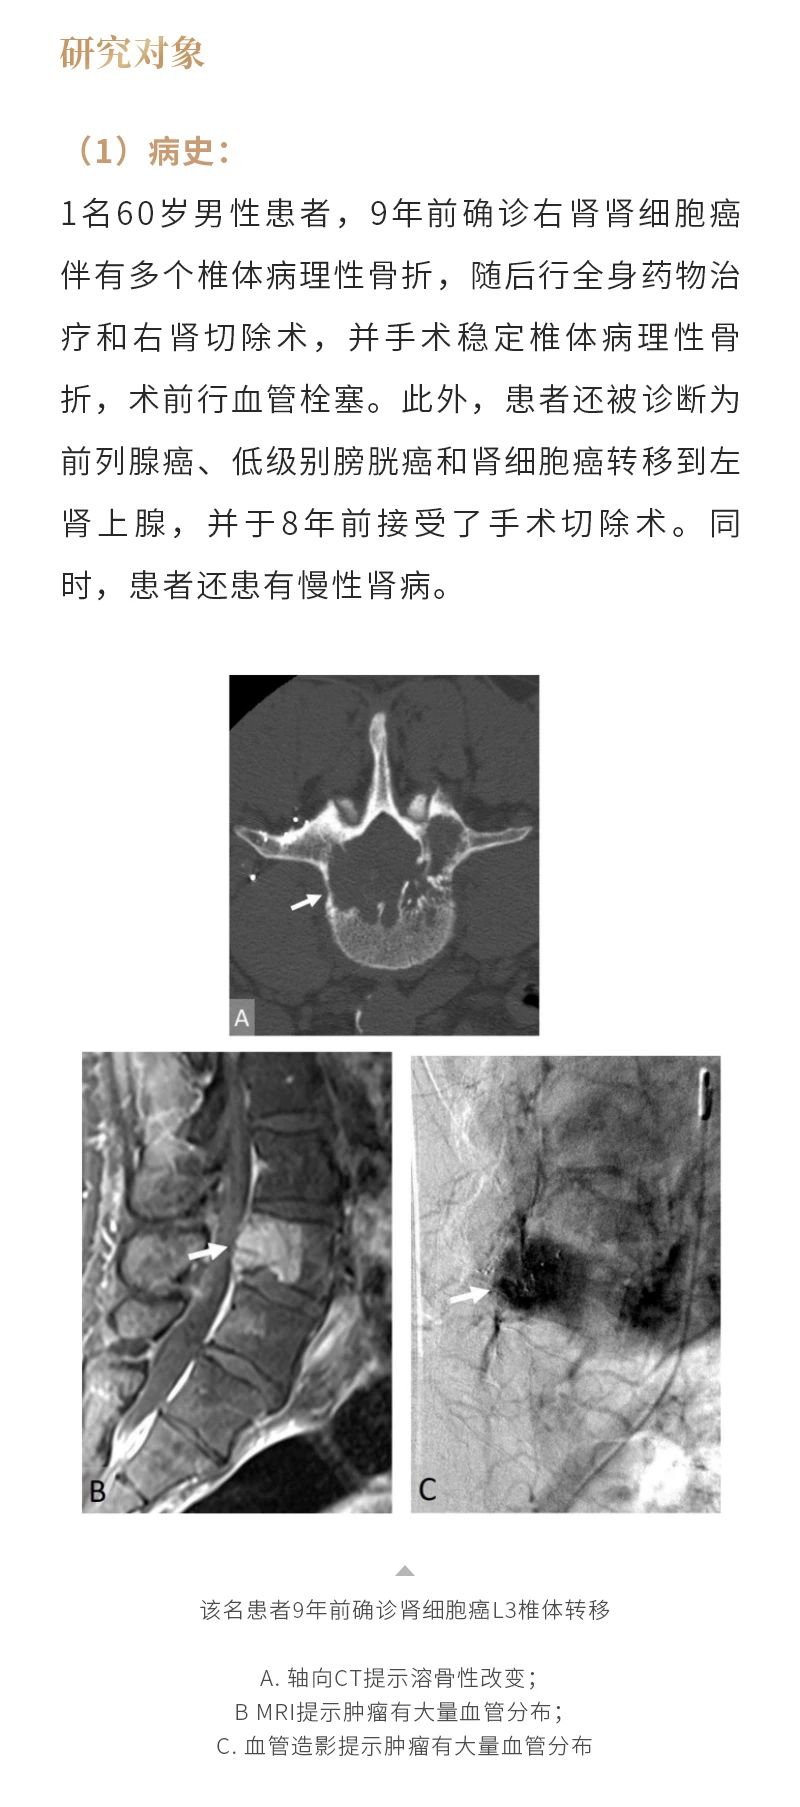

ELF ? 復(fù)合式冷熱消融系統(tǒng)